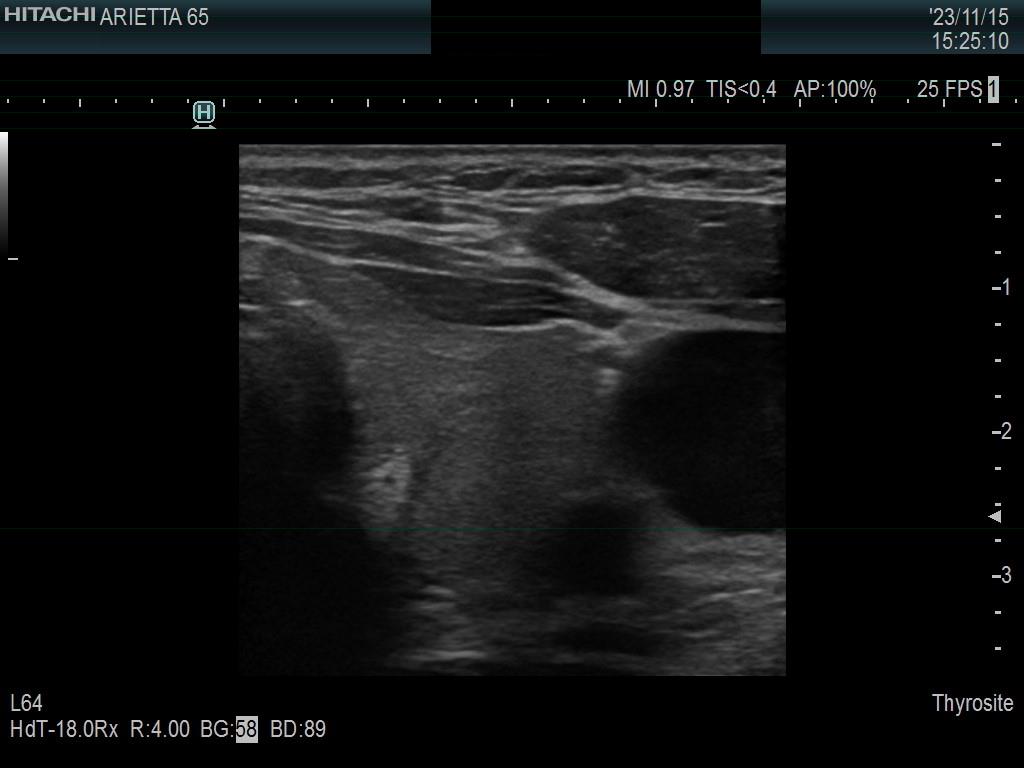

Ultrasonography. The thyroid was minimally hypoechoic. The echogenicity of the dorsal part of the left lobe where the nodule was previously described did not differ from other parts of the thyroid. There was a connective tissue running ventral to this part of the lobe and hypoechoic areas were found upper and dorsal to this. Neither halo nor perinodular blood flow was present.

The area in question did not correspond to a pathological nodule. It seemed to be circumscribed because of the presence of connective tissue and thyroid vessels.

A follicular tumor must have a capsule which ultrasound sign, either a complete halo and/or perinodular blood flow are present in more than 95% of cases. Both features were absent in this case.